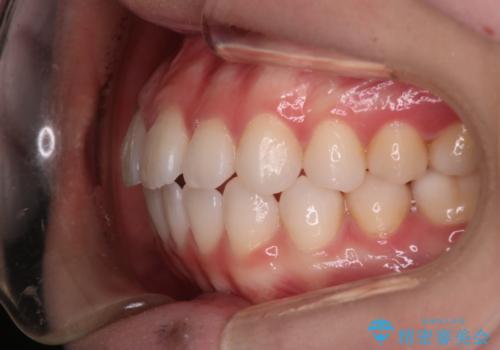

【審美装置】前歯で噛めない!抜歯しないで治したい

- 前歯の捻転とかみ合わせを主訴に来院されました。今回は抜歯をせずにIPRを実施し、並べる計画を立てました。

ワイヤー矯正を行いながら、顎間ゴムを患者さまにご協力していただき、短い期間で終了できました。